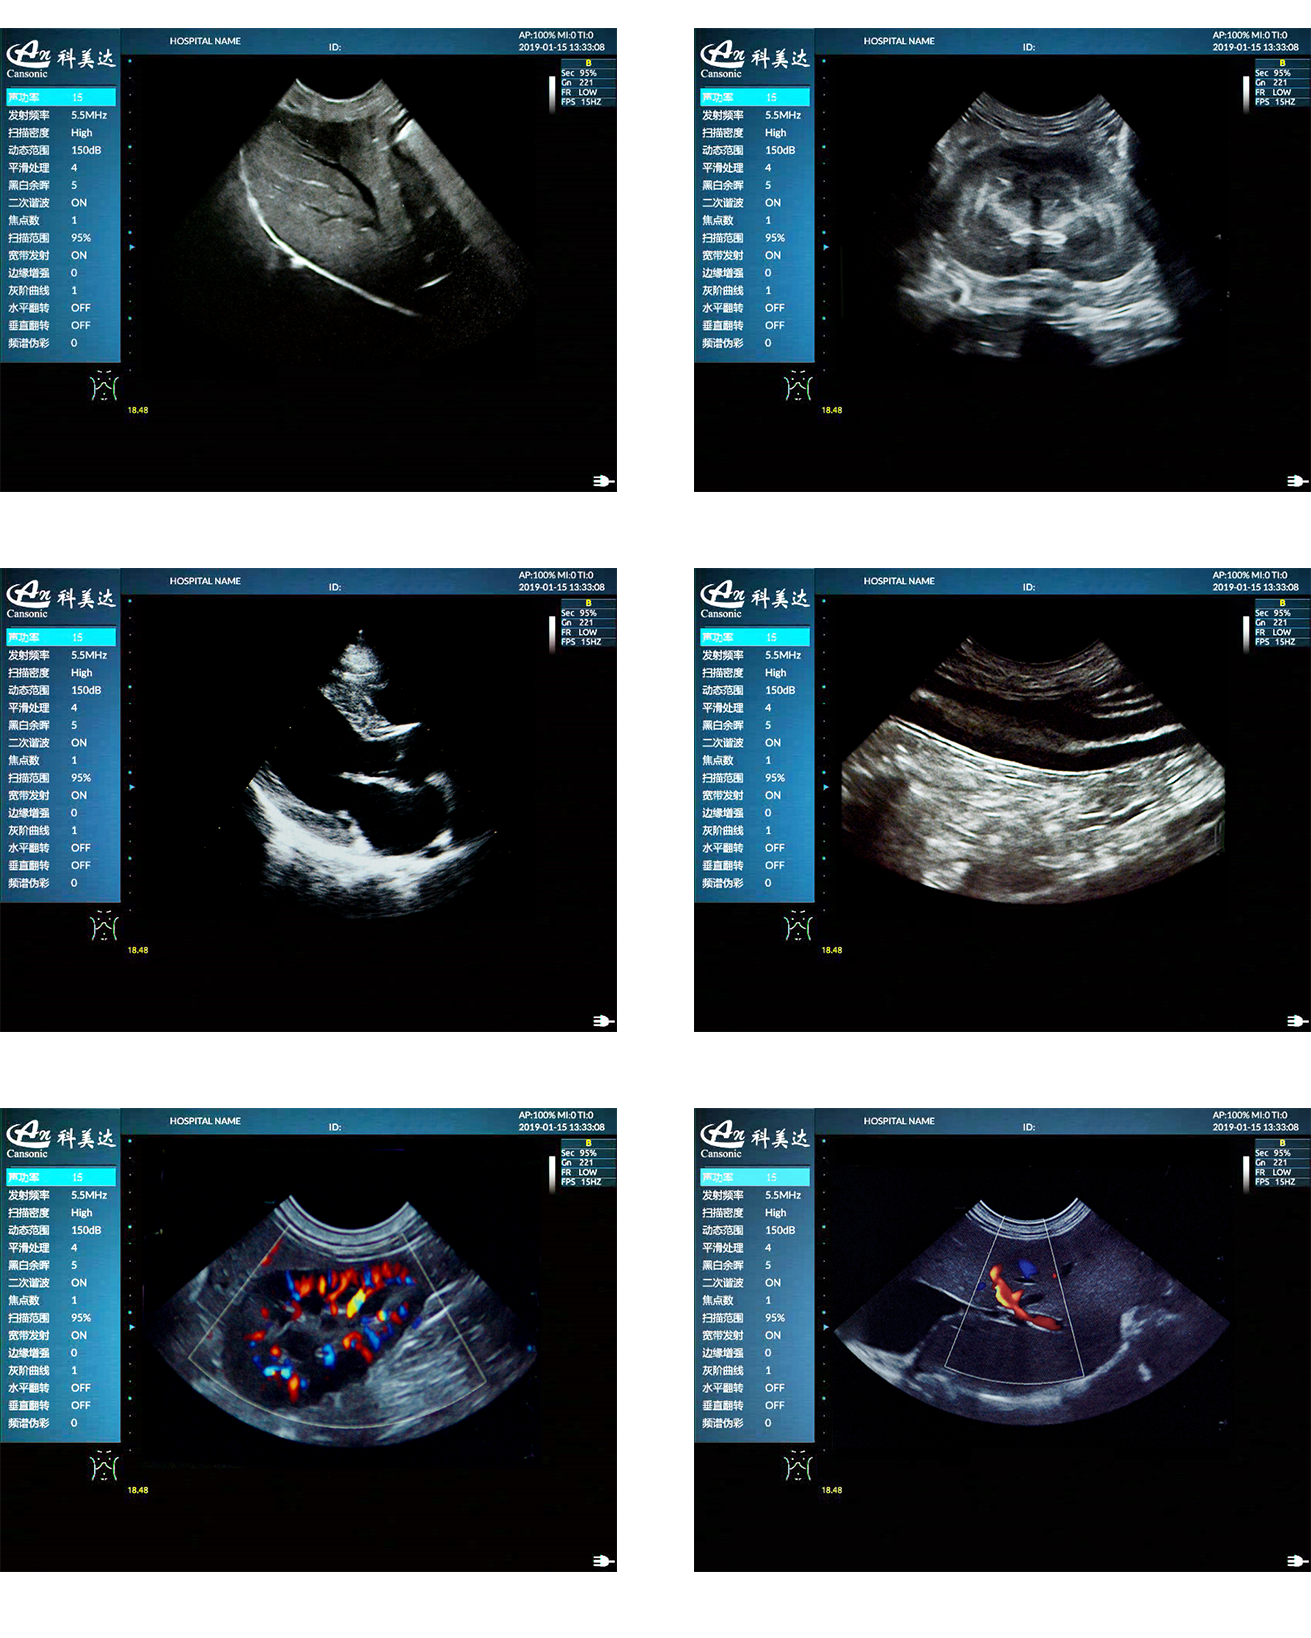

临床图示